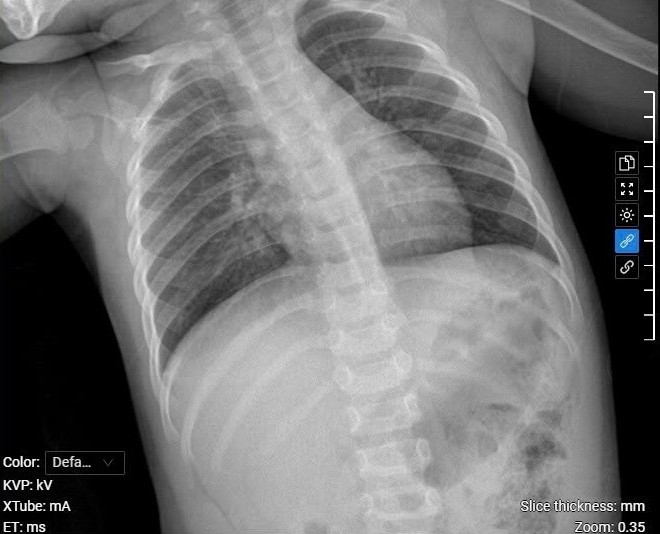

Kết quả chụp X-quang cho thấy phổi bé Hiền bị ứ khí, gây khó thở, khò khè. Ảnh: Bệnh viện Đa khoa Tâm Anh